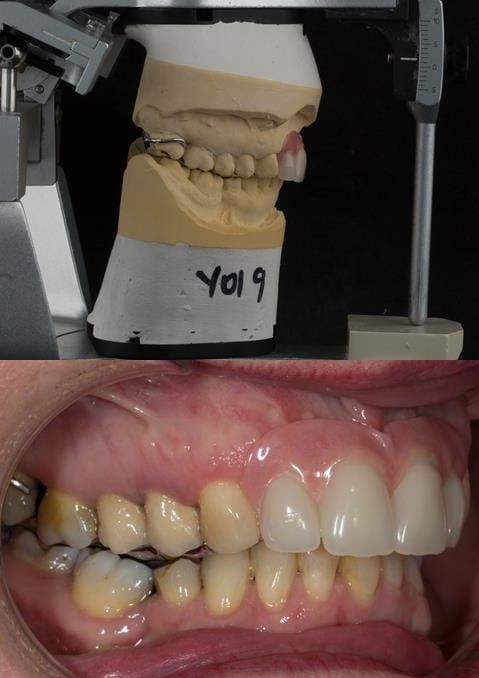

- UR2 peri-radicular periodontitis with a peri-radicular area on the root apex. Retrograde amalgam filling from a previous apicectomy. No visible root canal or root canal filling. Large circumferential marginal gap between the crown and tooth. Large post and core present. Very little tooth structure remaining resulting in a fragile tooth with increased potential for fracture.

- UR1 peri-radicular periodontitis with a small peri-radicular area on the root apex with wide blunderbuss apex. Radio-opaque root canal filling present approximately 3 mm short of the radiographic apex. Large circumferential marginal gap between the crown and tooth. Large post and core present. Very little tooth structure remaining resulting in a fragile tooth with increased potential for fracture.

- UL1 peri-radicular periodontitis with a peri-radicular area on the root apex. Retrograde amalgam filling from a previous apicectomy. Visible root canal space with no sign of root canal filling. Large circumferential marginal gap between the crown and tooth. Large post and core present. Very little tooth structure remaining resulting in a fragile tooth with increased potential for fracture.

- UL2 peri-radicular periodontitis with a peri-radicular area on the root apex. No visible root canal or root canal filling. Large circumferential marginal gap between the crown and tooth. Large post and core present. Very little tooth structure remaining resulting in a fragile tooth with increased potential for fracture.

- High smile line showing gum above gingival zeniths of upper front teeth when smiling. Aesthetic failure of the upper four incisors with inflammation of the gingivae and mis-match of the gingival zenith levels.

- Other than the maxillary incisors the remaining dentition was in marginally better condition being moderately to heavily restored. Many will probably require replacement and restoration from time to time mainly from wear and tear owing to occlusal forces.